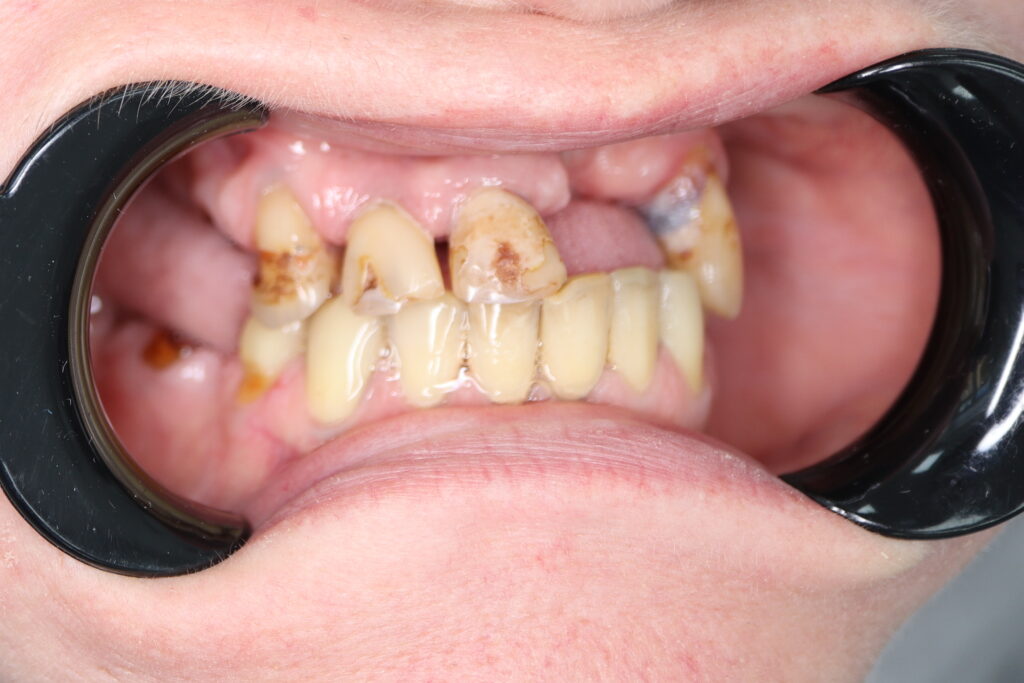

Ситуация до лечения

Жалобы: Пациент обратился с целью тотальной имплантации верхней челюсти.

Диагноз: Частичная вторичная адентия верхней челюсти.

пациент до тотальной имплантации